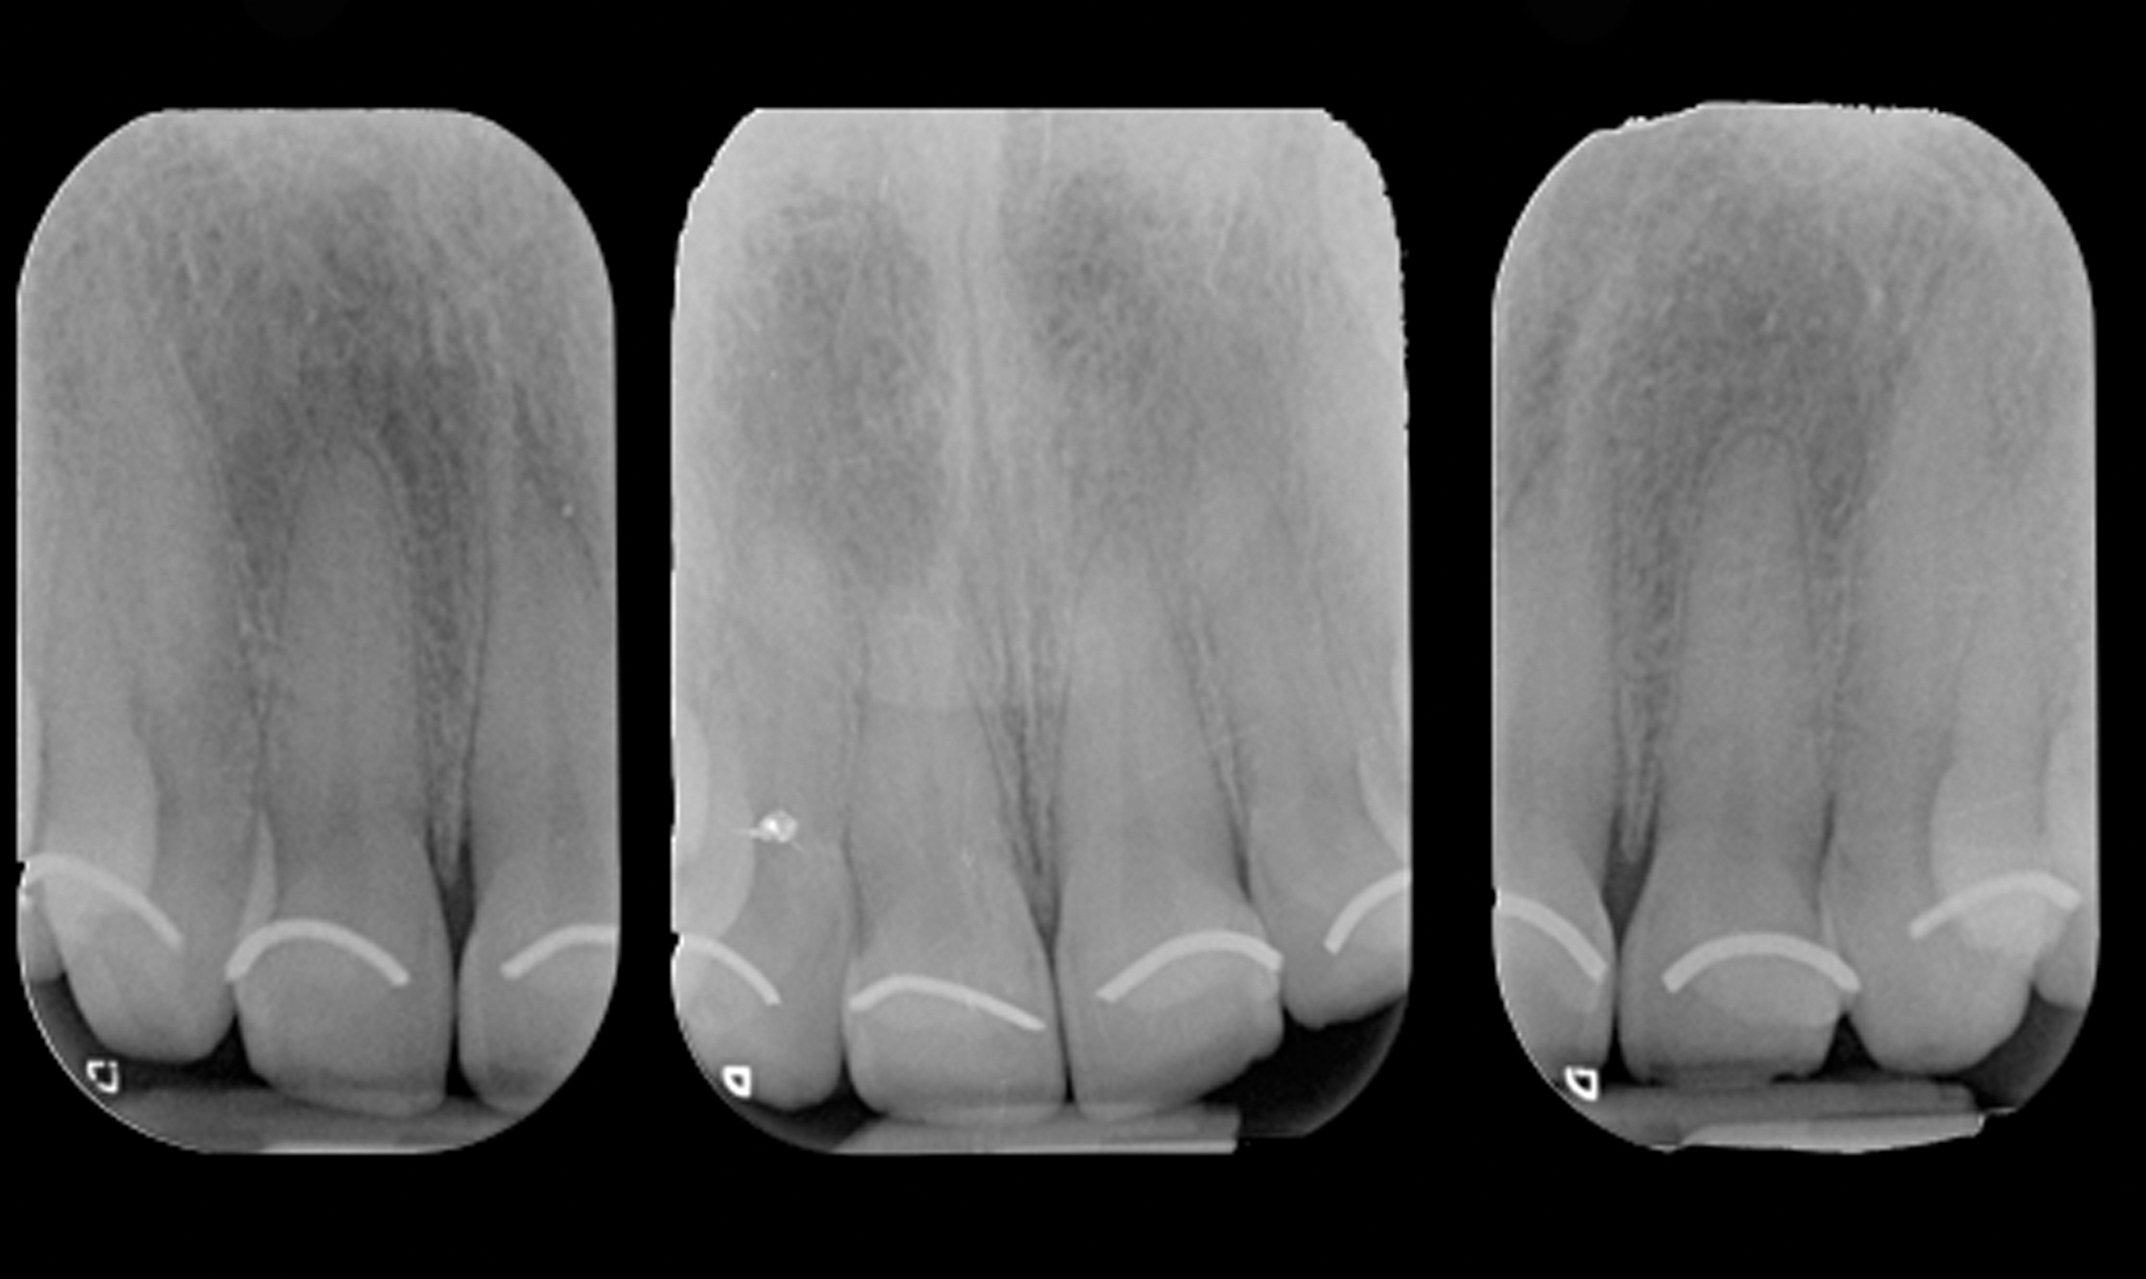

The authors developed what they call the altered eruption x-ray technique (AltErX) whereby a periapical radiograph is taken after placement of a radiopaque flowable composite material or orthodontic wire at the gingival margin to detect discrepancies between the anatomic and clinical crown (Figure 9 and Figure 10). The radiograph should be as perpendicular to the tooth as possible, because excessive x-ray angulation may give false diagnosis in patients with small or high palates. To confirm the presence of an altered eruption, further and more invasive diagnostic procedures are required. If an altered eruption is suspected, bone sounding under local anesthesia should be carried out before periodontal surgery to confirm its presence and discern between APE subclasses.19

Fig 9. Placement of orthodontic wire at the gingival margins (Fig 9), and radiographs showing radiopaque markers for detection of CEJ and gingival margins (Fig 10).

Fig 10. Placement of orthodontic wire at the gingival margins (Fig 9), and radiographs showing radiopaque markers for detection of CEJ and gingival margins (Fig 10).